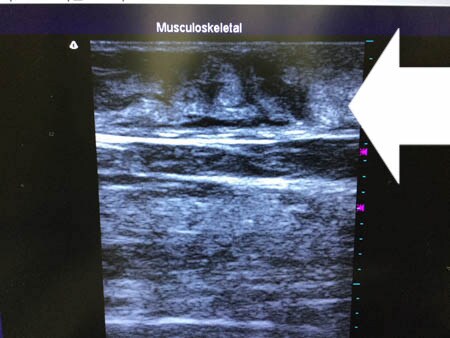

いつものように3Dタッチビュー(超音波)で

皮下脂肪層を評価してみましょう。

左太もも前面。

上の画像の部分の皮下脂肪層をつまんでみましょう。

同様に右太もも前面。 ↓ ↓ ↓